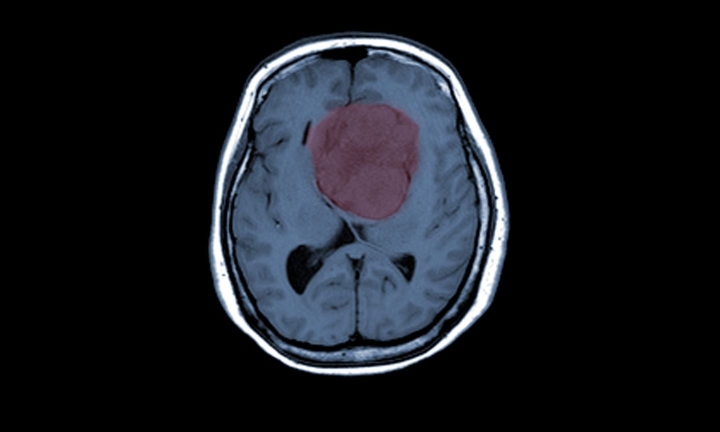

Разработанная для применения с такими радиохирургическими системами, как ZAP-X от Zap, платформа Axon специально предназначена для планирования краниальных процедур стереотаксической радиохирургии (SRS). SRS подразумевает точное нацеливание радиохирургических лучей с тысяч потенциальных углов для уменьшения размера злокачественных опухолей, при этом здоровые ткани мозга остаются нетронутыми.